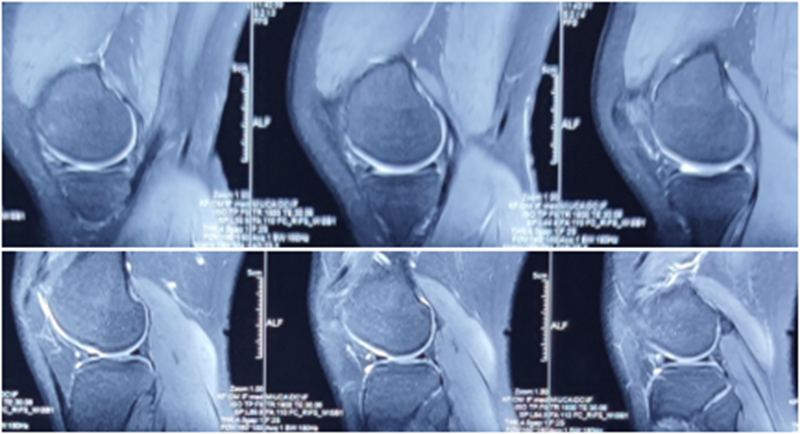

术前MRI

MRI检查评估ACL-R术后——韧带连续性信号好、方向好、愈合快,没有Cyclops综合征。